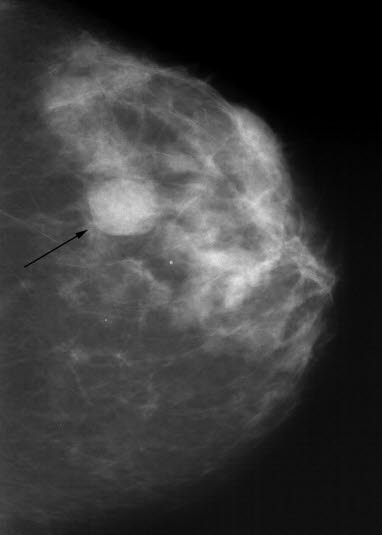

Mammografi, cysteBrystene betegnes på fagspråket for mammae. De består av et omfattende nett av melkekjertler og utførselsganger som ender i brystvorten. Egenundersøkelse av brystene anbefales for alle kvinner. På den måten blir kvinnen kjent med hvordan brystene er, og hun vil raskere bli oppmerksom dersom det oppstår en forandring.

Kuler i brystene forekommer ofte og de aller fleste er godartede. Det kan være væskefylte kuler (cyster) eller bindevevs-kuler (fibroadenomer). Godartede kuler har ofte så typiske trekk at de lett lar seg gjenkjenne når legen undersøker brystene. De har glatt overflate, er lett å avgrense, har myk og elastisk fasthet. Forandringer med uregelmessig overflate, påfallende hard konsistens og som er vanskelig å avgrense fra annet vev er funn som tilsier at videre undersøkelser er påkrevet. Mammografi er da som regel den første undersøkelsen som gjøres.